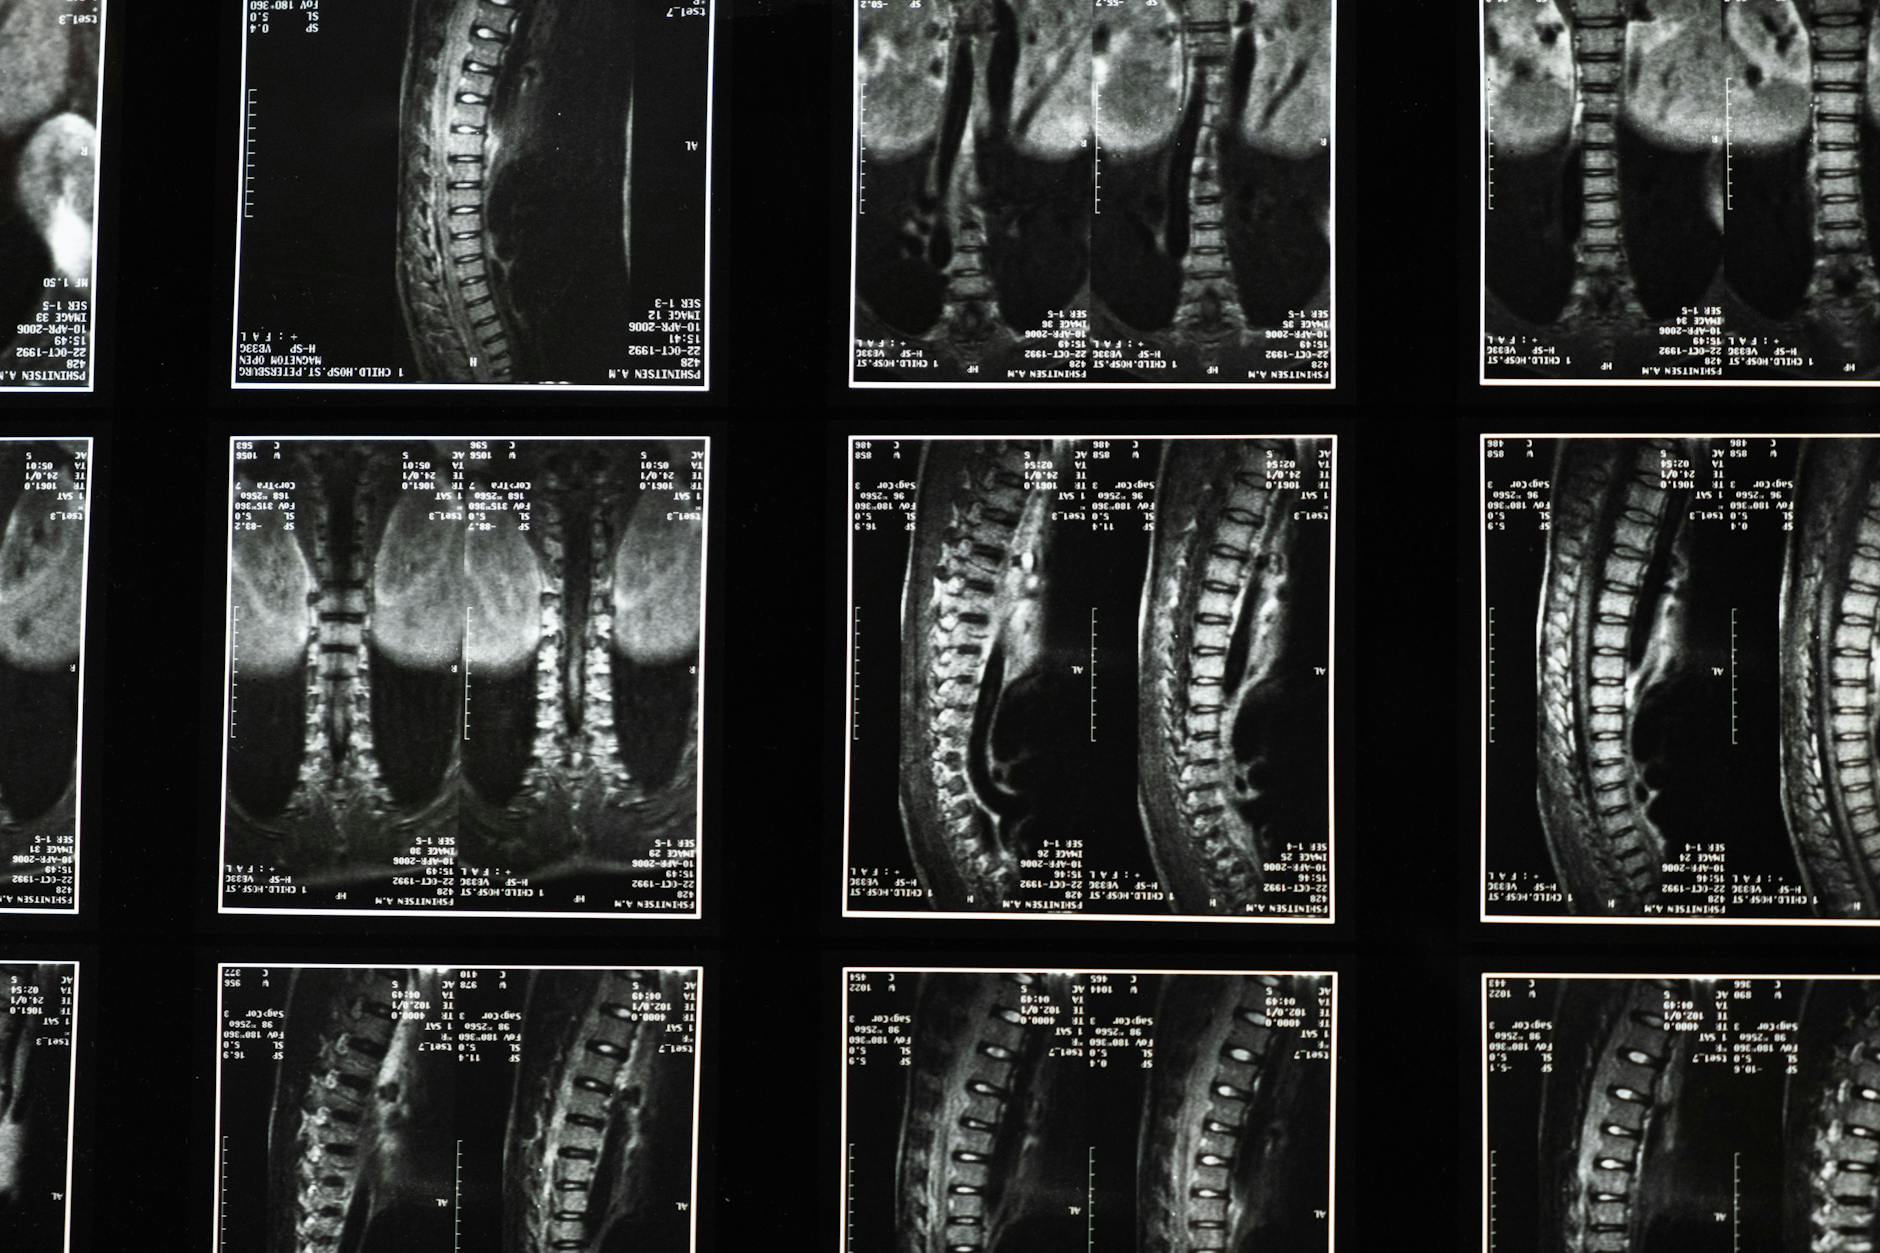

Research from the Wakayama Spine Study, published in *Osteoarthritis and Cartilage* in 2014, found that over 90 percent of men and women aged 50 and older show signs of disc degeneration on imaging. Cedars-Sinai reports that approximately 90 percent of adults over 60 have disc degeneration visible on MRI, yet many of them experience no symptoms at all. So the presence of degeneration does not automatically mean pain or disability, but when symptoms do appear, knowing what to look for matters enormously. This article walks through each of the nine signs in detail, explains the underlying mechanics, discusses when symptoms cross the line from inconvenience into medical urgency, and covers what the research says about who is most affected and why. If you or someone you care for is dealing with unexplained back pain, nerve symptoms, or creeping stiffness, the information below should help clarify what the body may be signaling.

These numbers make an important point: spine degeneration is not a disease in the way most people think of the word. It is closer to a universal aging process, like graying hair or wrinkling skin. The clinical question is not whether degeneration is present but whether it is producing symptoms and, if so, how severely those symptoms affect daily life. Many people with significant degeneration on imaging live without pain, while some with relatively mild changes experience debilitating symptoms. The relationship between structural damage and experienced pain is looser than most people assume, which is both reassuring and frustrating. It means that an alarming MRI report does not necessarily predict a painful future, but it also means that the source of a person’s pain can be difficult to pinpoint with certainty.